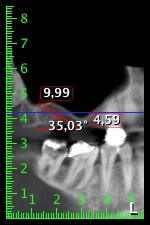

About six months after teeth 16 and 14 were extracted, a digital volume tomography (DVT, Planmeca) examination was performed for planning and risk minimization purposes. It clearly showed that the bone had not regenerated to the desired volume (Fig. 2 to 7).

Image 2 to 7: DVT with greatly reduced horizontal bone volume.

A sinus floor elevation is required in both region 16 and region 14 to guarantee a fixed restoration based on at least two implants. Relatively large-scale bone augmentation is required due to the residual bone volume being extremely low in this case. Major bone augmentation procedures are invasive and linked to higher patient morbidity, as well as being time-consuming and expensive. It is more difficult to predict the results of the treatment and the risk of failure is increased. The patient was informed of the increased risk and was offered a removable solution, which she consistently rejected.

To restrict the augmentation to region 14, and in consultation with the patient, it was planned that implant 16 would be placed, inclined, in the dorso-cranial direction (Fig. 8).